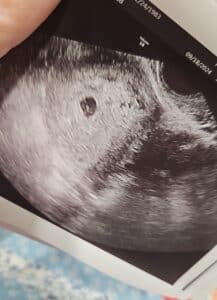

The baby is growing!!!! Baby Forbes is due May 17, 2025!!!!!!

I am 6 weeks pregnant!

Patient age: 40

Tubal ligation type: Tubal clips (clamps)

Patient hometown: Fort Lawn, South Carolina